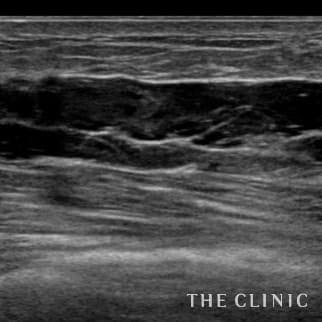

35歳 女性 アクアフィリング(アクアリフト)豊胸のお悩みのアクアフィリング(アクアリフト)豊胸除去

半年前に他院でアクアフィリング豊胸を行いましたが、バストの変形やしこりに悩み除去手術を希望しました。 見た目には右胸内側上部と左胸内側下部に不自然な盛り上がりとしこりを認めました。エコーではアクアフィリングのしこりが散在し、一部は塊になっていました。 アクアフィリングは生理食塩水で溶解されますが、完全には溶解せず固まっていますので、吸引して除去しました。治療の概要 アクアフィリング除去+コンデンスリッチ豊胸:乳腺用エコーを用いて、バスト内の状態を確認。その後、生理食塩水でアクアフィリングを溶解する。溶解仕切れない場合には、注射器で吸い出し除去。アクアフィリング の除去後、バストの皮下にコンデンスリッチファット(老化細胞や不純物を取り除いて濃縮させた自己脂肪)を注入。 施術費用 アクアフィリング 除去(会員料金):¥600,000(税込¥660,000)/溶解1部位